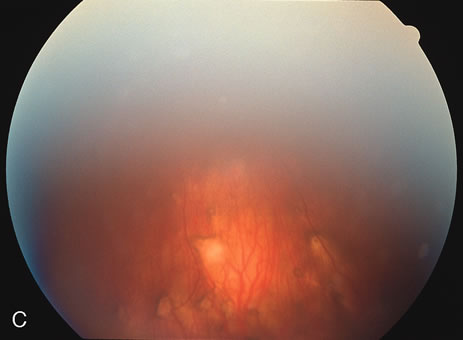

Some patients present with subretinal bands that extend between chorioretinal scars. In addition there may be initial active yellow choroidal lesions that subsequently become atrophic. Vitreous cells are usually present although they may be few and difficult to detect. Visual acuity loss in these cases may be due to active choroidal neovascularization, subretinal bands under the fovea, or from cystoid macular edema. The vast majority of affected patients are women with a mean age of 27 years and both eyes are usually involved. The affected individuals tend to be myopic.49 The age range is from 6 years to 76 years and there is no racial predilection.40 Whether it is a separate disease or a more severe form of multifocal choroiditis is controversial (Figs. 10 and 11). Aggressive therapy is warranted because it has a poorer prognosis than most cases of multifocal choroiditis. This syndrome has been called either diffuse subretinal fibrosis or progressive subretinal fibrosis syndrome.

Fig. 10. A. Fundus photograph showing the subretinal fibrosis extending from the disc to the periphery in a case of diffuse subretinal fibrosis. B. Fundus photograph showing the marked fibrosis in the midperiphery. C. Multifocal choroiditis type lesions noted in the inferior retina.